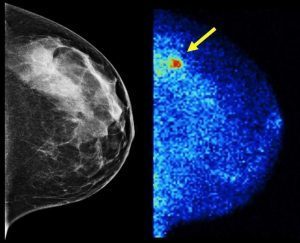

Breast Density may be leading risk factor for Breast Cancer – Reuters Health Researchers examined data on more than 18,000 women with breast malignancies and 184,000 women the same age without breast cancer. They found breast density appeared to be the biggest indicator of cancer risk, even more than other common risk factors like family … More Your Breast Density – your Destiny, know it.